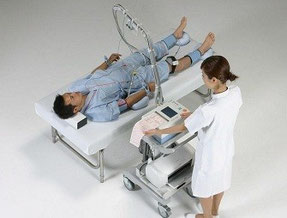

ABI/PWV検査(動脈硬化検査)

手と足の血圧を比較し、脈の伝わり方を調べることで、動脈硬化の程度や早期の血管障害を調べることができます。検査時間は5分程度です。

測定した血圧を元に機械でABI(足関節/上腕血圧比)とPWV(脈波伝播速度)を測定します。ABIの数値が0.9以下の場合は動脈硬化が強く疑われ、さらにPWVの数値が1350(年齢によって異なる)以上の場合は、動脈硬化の進行を示します。くも膜下出血や、脳梗塞、狭心症や心筋梗塞などの病気にかかりやすくなっているため、高血圧や脂質異常症の方は積極的な治療が必要となります。

ABI/PWV測定風景